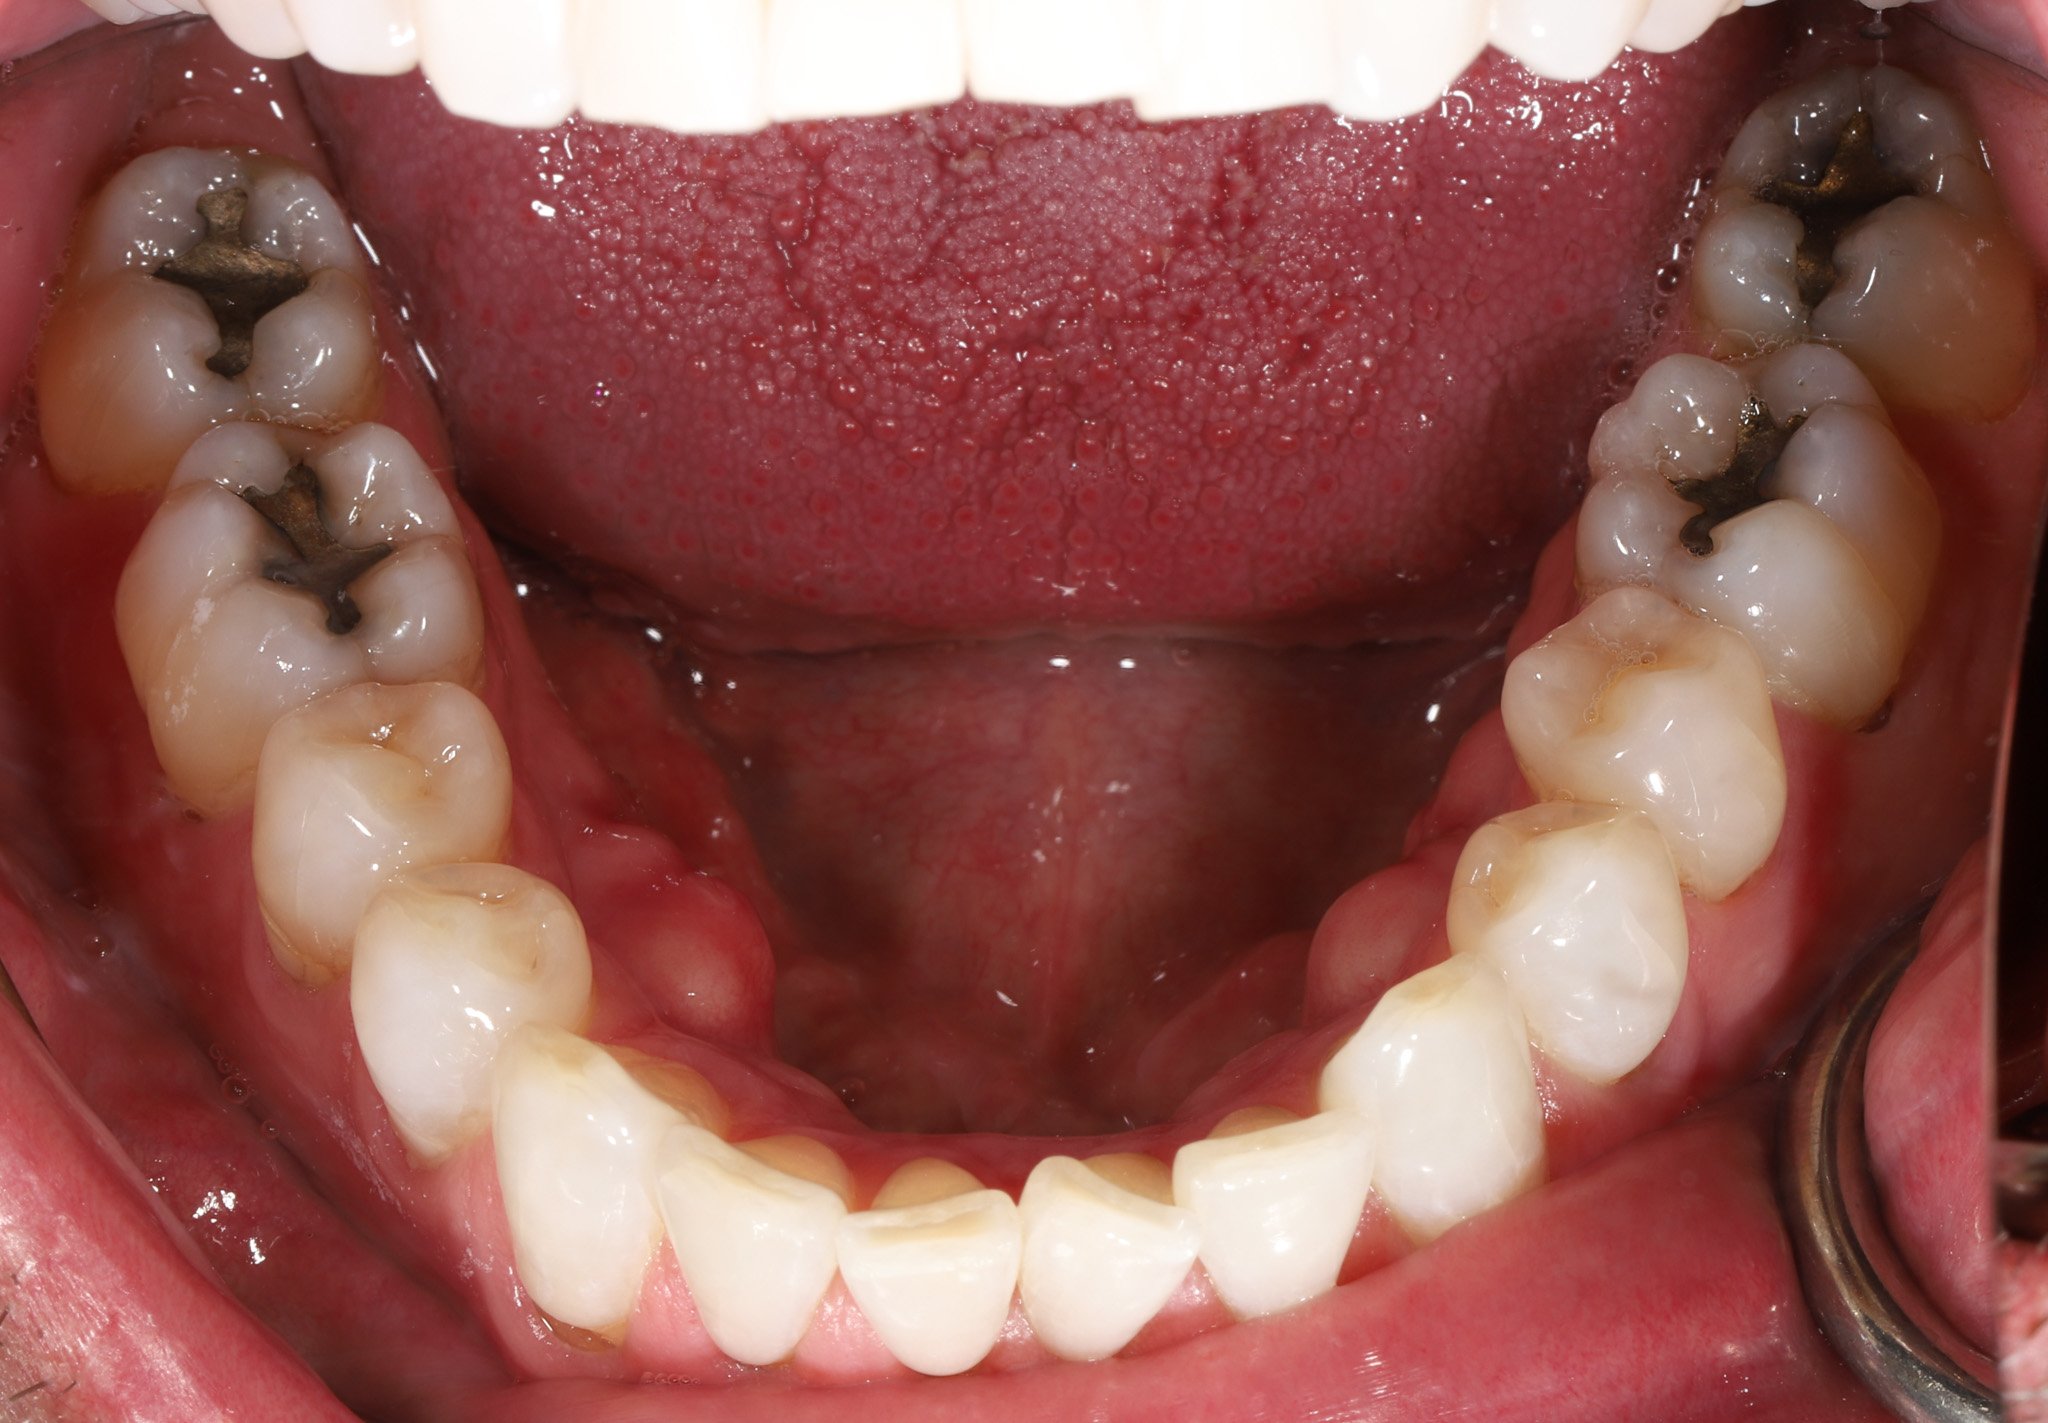

Open mouth displaying upper and lower molars with multiple cavities and decay.

Before: Silver fillings, leakage, cracks, decay

Open mouth showing upper and lower teeth with healthy gums and tongue

After: Combination of bonded porcelain and composite to restore teeth